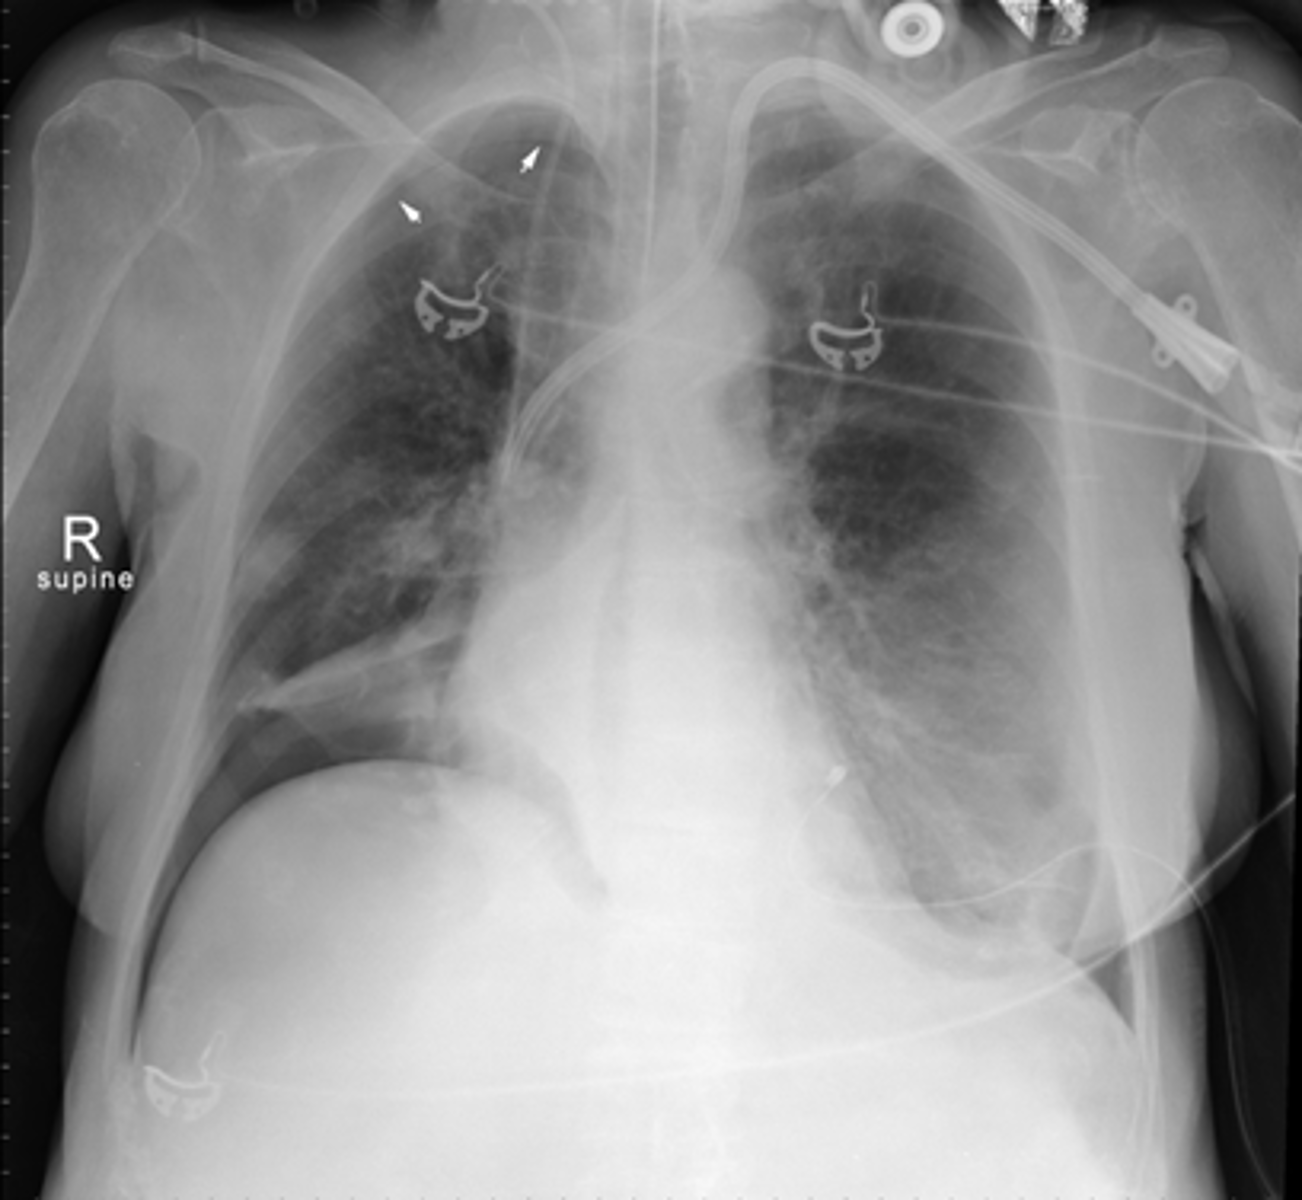

CT with IV contrast of SBO.

SOLID BLACK ARROWS: multiple fluid- and contrast filled dilated loops of small bowels.

WHITE ARROWS: Collapsed colon

DOTTED BLACK ARROW: Right renal cyst